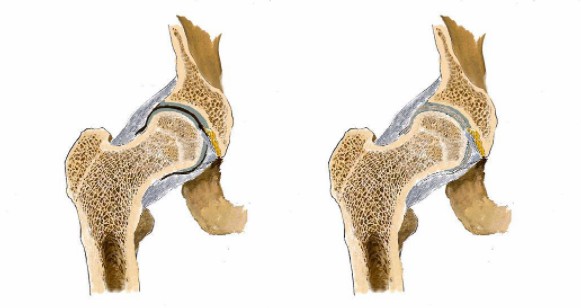

看男孩不說(shuō)話,醫(yī)生繼續(xù)說(shuō)道:“你的HLA-B27顯示陰性,如果是陽(yáng)性就可以確診是強(qiáng)直性脊柱炎,現(xiàn)在只能排查……如果確診是強(qiáng)直性脊柱炎,就要就要及早治療,因?yàn)檫@個(gè)病是不可逆的,我們只能延緩它病程進(jìn)度……”

醫(yī)生對(duì)著拍好的片子來(lái)來(lái)回回看了好幾遍,男孩就一直站在他邊上,他知道醫(yī)生接下來(lái)說(shuō)的話將決定自己的一生。

“早上起床的時(shí)候有晨僵、背疼嗎?”

男孩先是一怔然后連忙說(shuō)“沒有!”

“最近是不是有過(guò)劇烈的運(yùn)動(dòng)?”

“前段時(shí)間,每天都會(huì)做卷腹。”

“你這沒事!腿痛就是有點(diǎn)水腫炎癥導(dǎo)致的,注意休息鍛煉適度就會(huì)好的。”